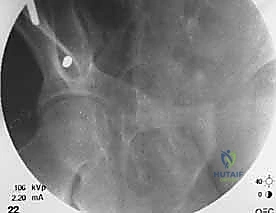

الخطوة الثانية: تحديد المعالم العظمية واستخدام الأشعة المرئية (C-Arm)

باستخدام جهاز الأشعة السينية المتحرك (Fluoroscopy) داخل غرفة العمليات، يقوم الدكتور هطيف بتحديد المعالم العظمية الدقيقة لضمان إدخال المسامير في الأماكن الأكثر كثافة وقوة في عظام الحوض (عادة فوق الحُق Supra-acetabular أو في العرف الحرقفي Iliac crest).